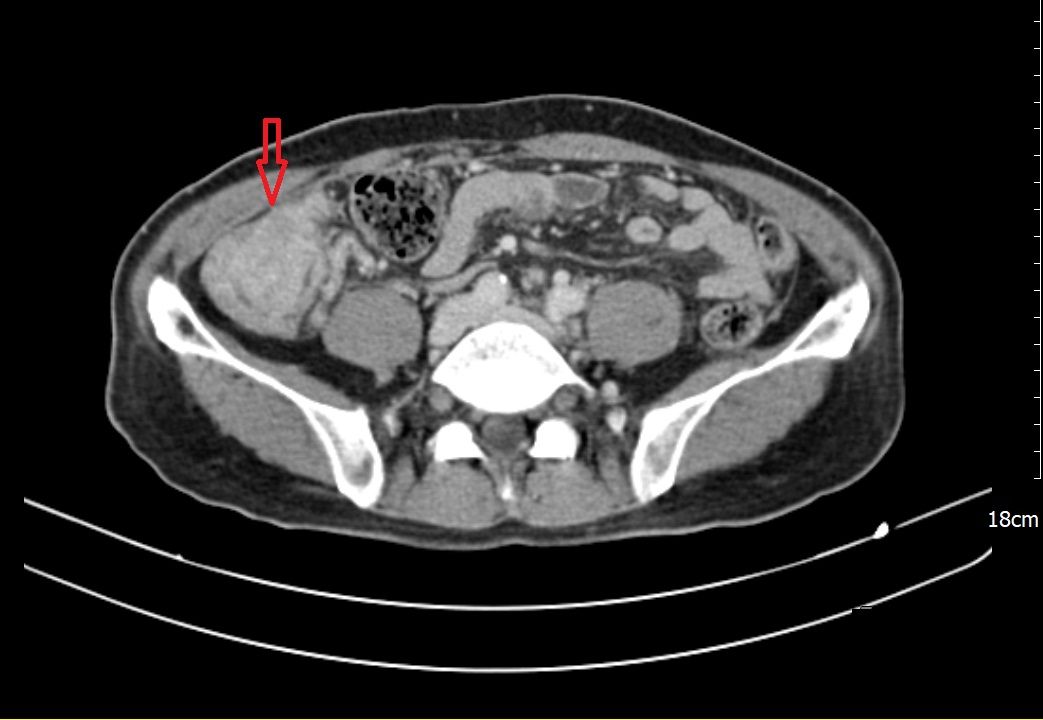

66 歲的陳先生自去年八、九月起,陸續出現全身倦怠、食慾不振、腹脹與腹瀉等情形,短短兩個月內體重減少約6公斤,因身體不適至義大癌治療醫院一般外科趙頌慈醫師門診求診,經檢查後發現,血紅素偏低並合併營養狀況不佳,影像檢查發現罹患多發性結腸癌,且腫瘤已擴散至腹腔,對病人與家屬而言是噩耗。

在腫瘤反應與身體條件允許下,醫療團隊進一步評估後,建議接受「腹腔高壓氣霧化學治療(PIPAC)」。此為以腹腔鏡進行的微創治療方式,將化療藥物於高壓環境中霧化,使藥物能較均勻分佈於腹腔內,作為部分腹膜癌病人之治療選項之一。陳先生完成一個療程、共三次「腹腔高壓氣霧化學治療(PIPAC)」 後,臨床症狀與檢查結果顯示病情獲得控制,相關評估指標亦呈現改善趨勢。